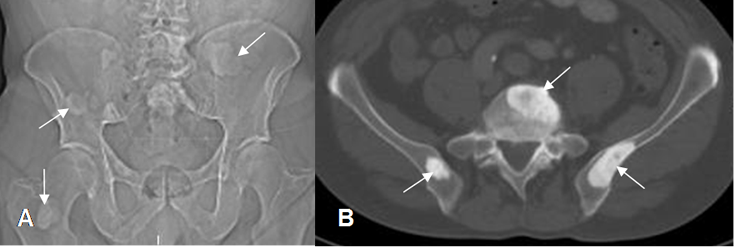

Fig 14. Tumor blástico.

A: Rx digital de pelvis y B: TAC axial. Múltiples lesiones densas en los iliacos, cuerpo de L5 y el cuello femoral derecho, por metástasis blásticas secundarias a tumor de próstata.